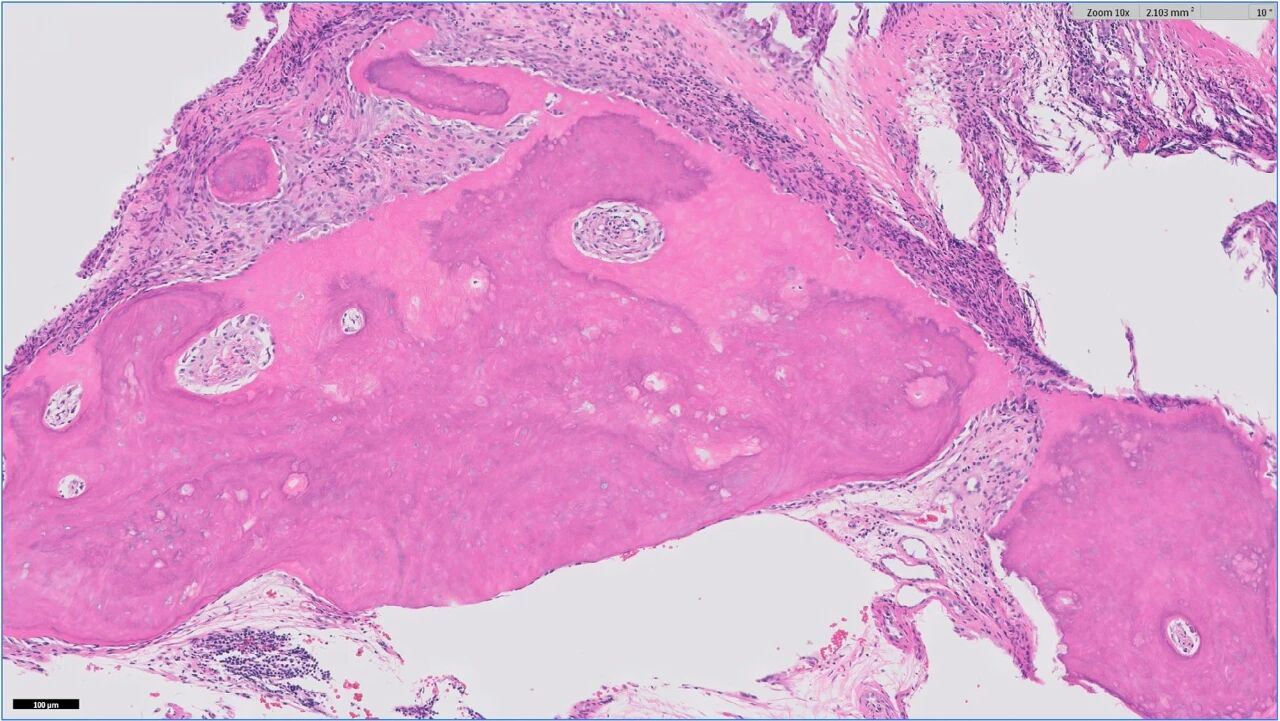

建议进行长骨活检,但因存在骨折风险被饲主拒绝。随后实施了鼻活检。组织病理学检查显示慢性、多灶性、中度嗜中性粒细胞至淋巴浆细胞性鼻炎。病理学结果支持骨质增厚是导致CT中鼻甲肥厚的原因,显示多灶性增厚的骨质呈不规则形态且矿化,但普遍缺乏细胞成分,未见正常骨代谢特征(下图)。

↑ 鼻部活检组织病理学图像显示多灶性不规则矿化骨质增生,该骨质多呈无细胞(坏死)状态。编织骨中未见明显反转线、霍氏骨小腔或破骨细胞。未见含有存活骨细胞的骨小腔。图示标本未经脱钙处理。